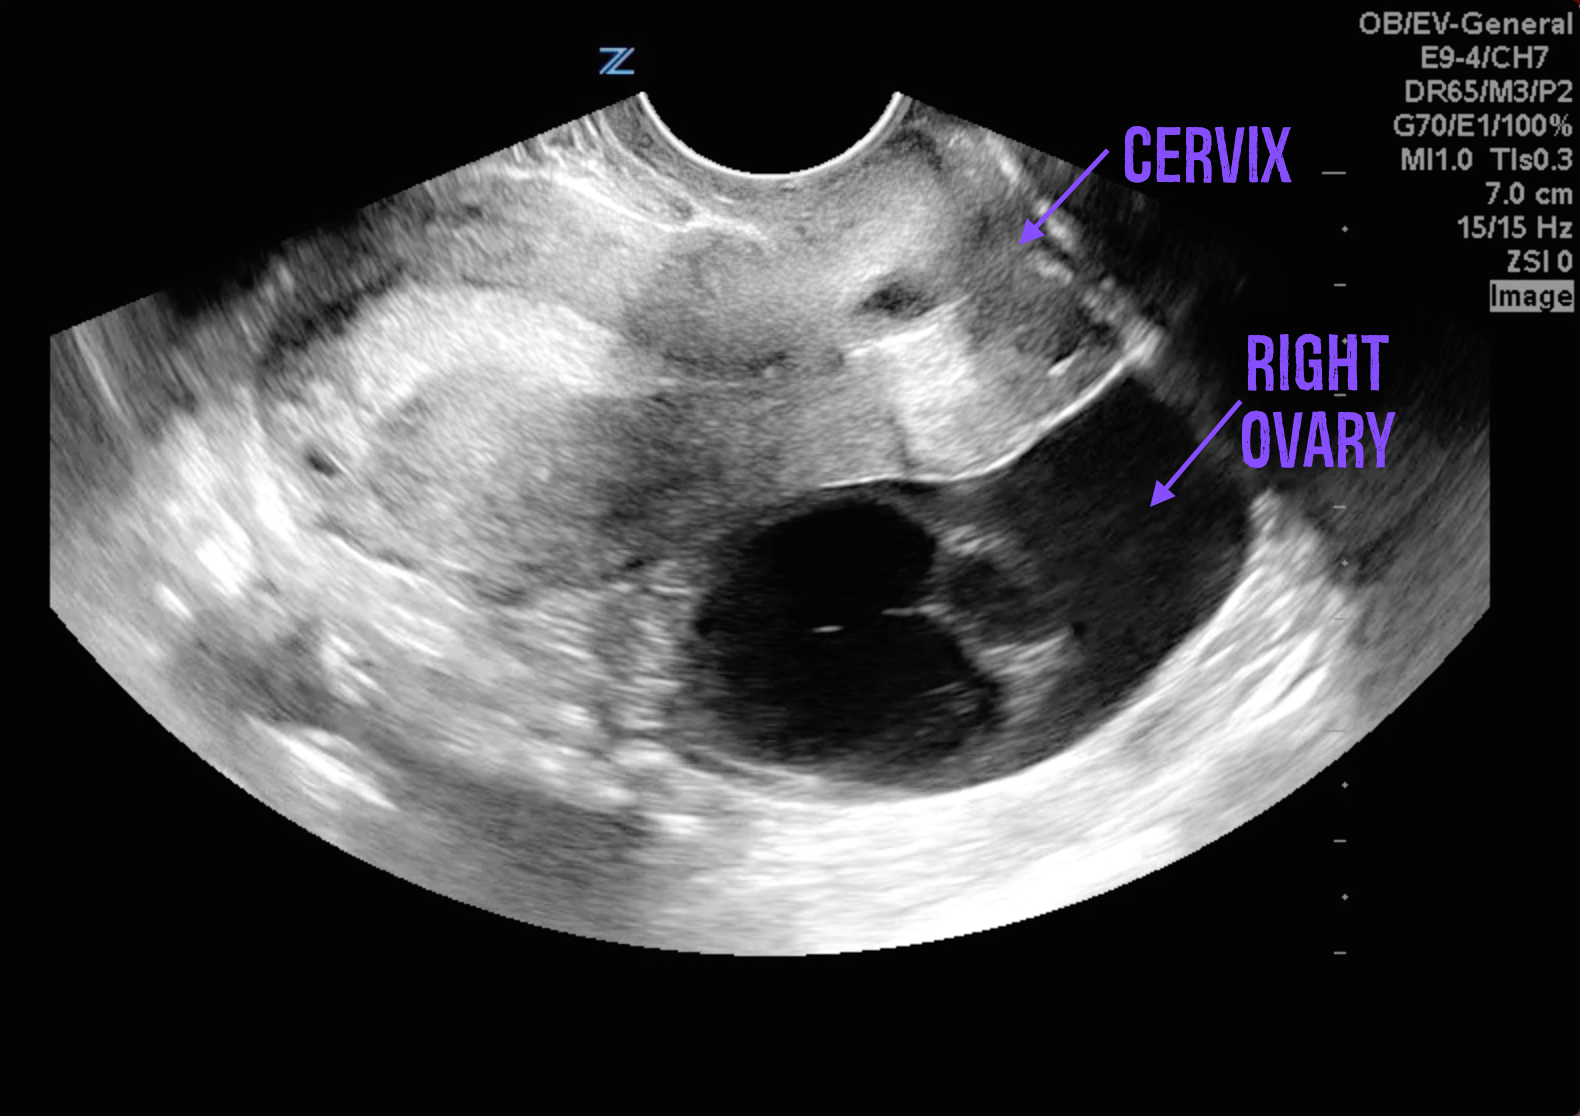

Sometimes what seems like a run-of-the-mill period symptom could be a sign of something more significant. For example, extremely painful cramps could indicate conditions like endometriosis or fibroids. Similarly, if you're experiencing cramps but no bleeding, it might be worth exploring the possibility of pregnancy or an ovarian cyst.